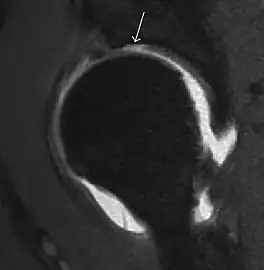

Most of the angles and measurements described in the plain radiograph section can be accurately reproduced on MRI. In addition, the superiority of MRI resolution with intra-articular contrast allows detection of labral and chondral abnormalities that may influence the choice of medical, percutaneous, or surgical management (Figure 9).[1]

Figure 9:

Sagittal T1 weighted image showing anterosuperior labral tear.[1] -

Sagittal T1 weighted image showing chondral lesion.[1] -